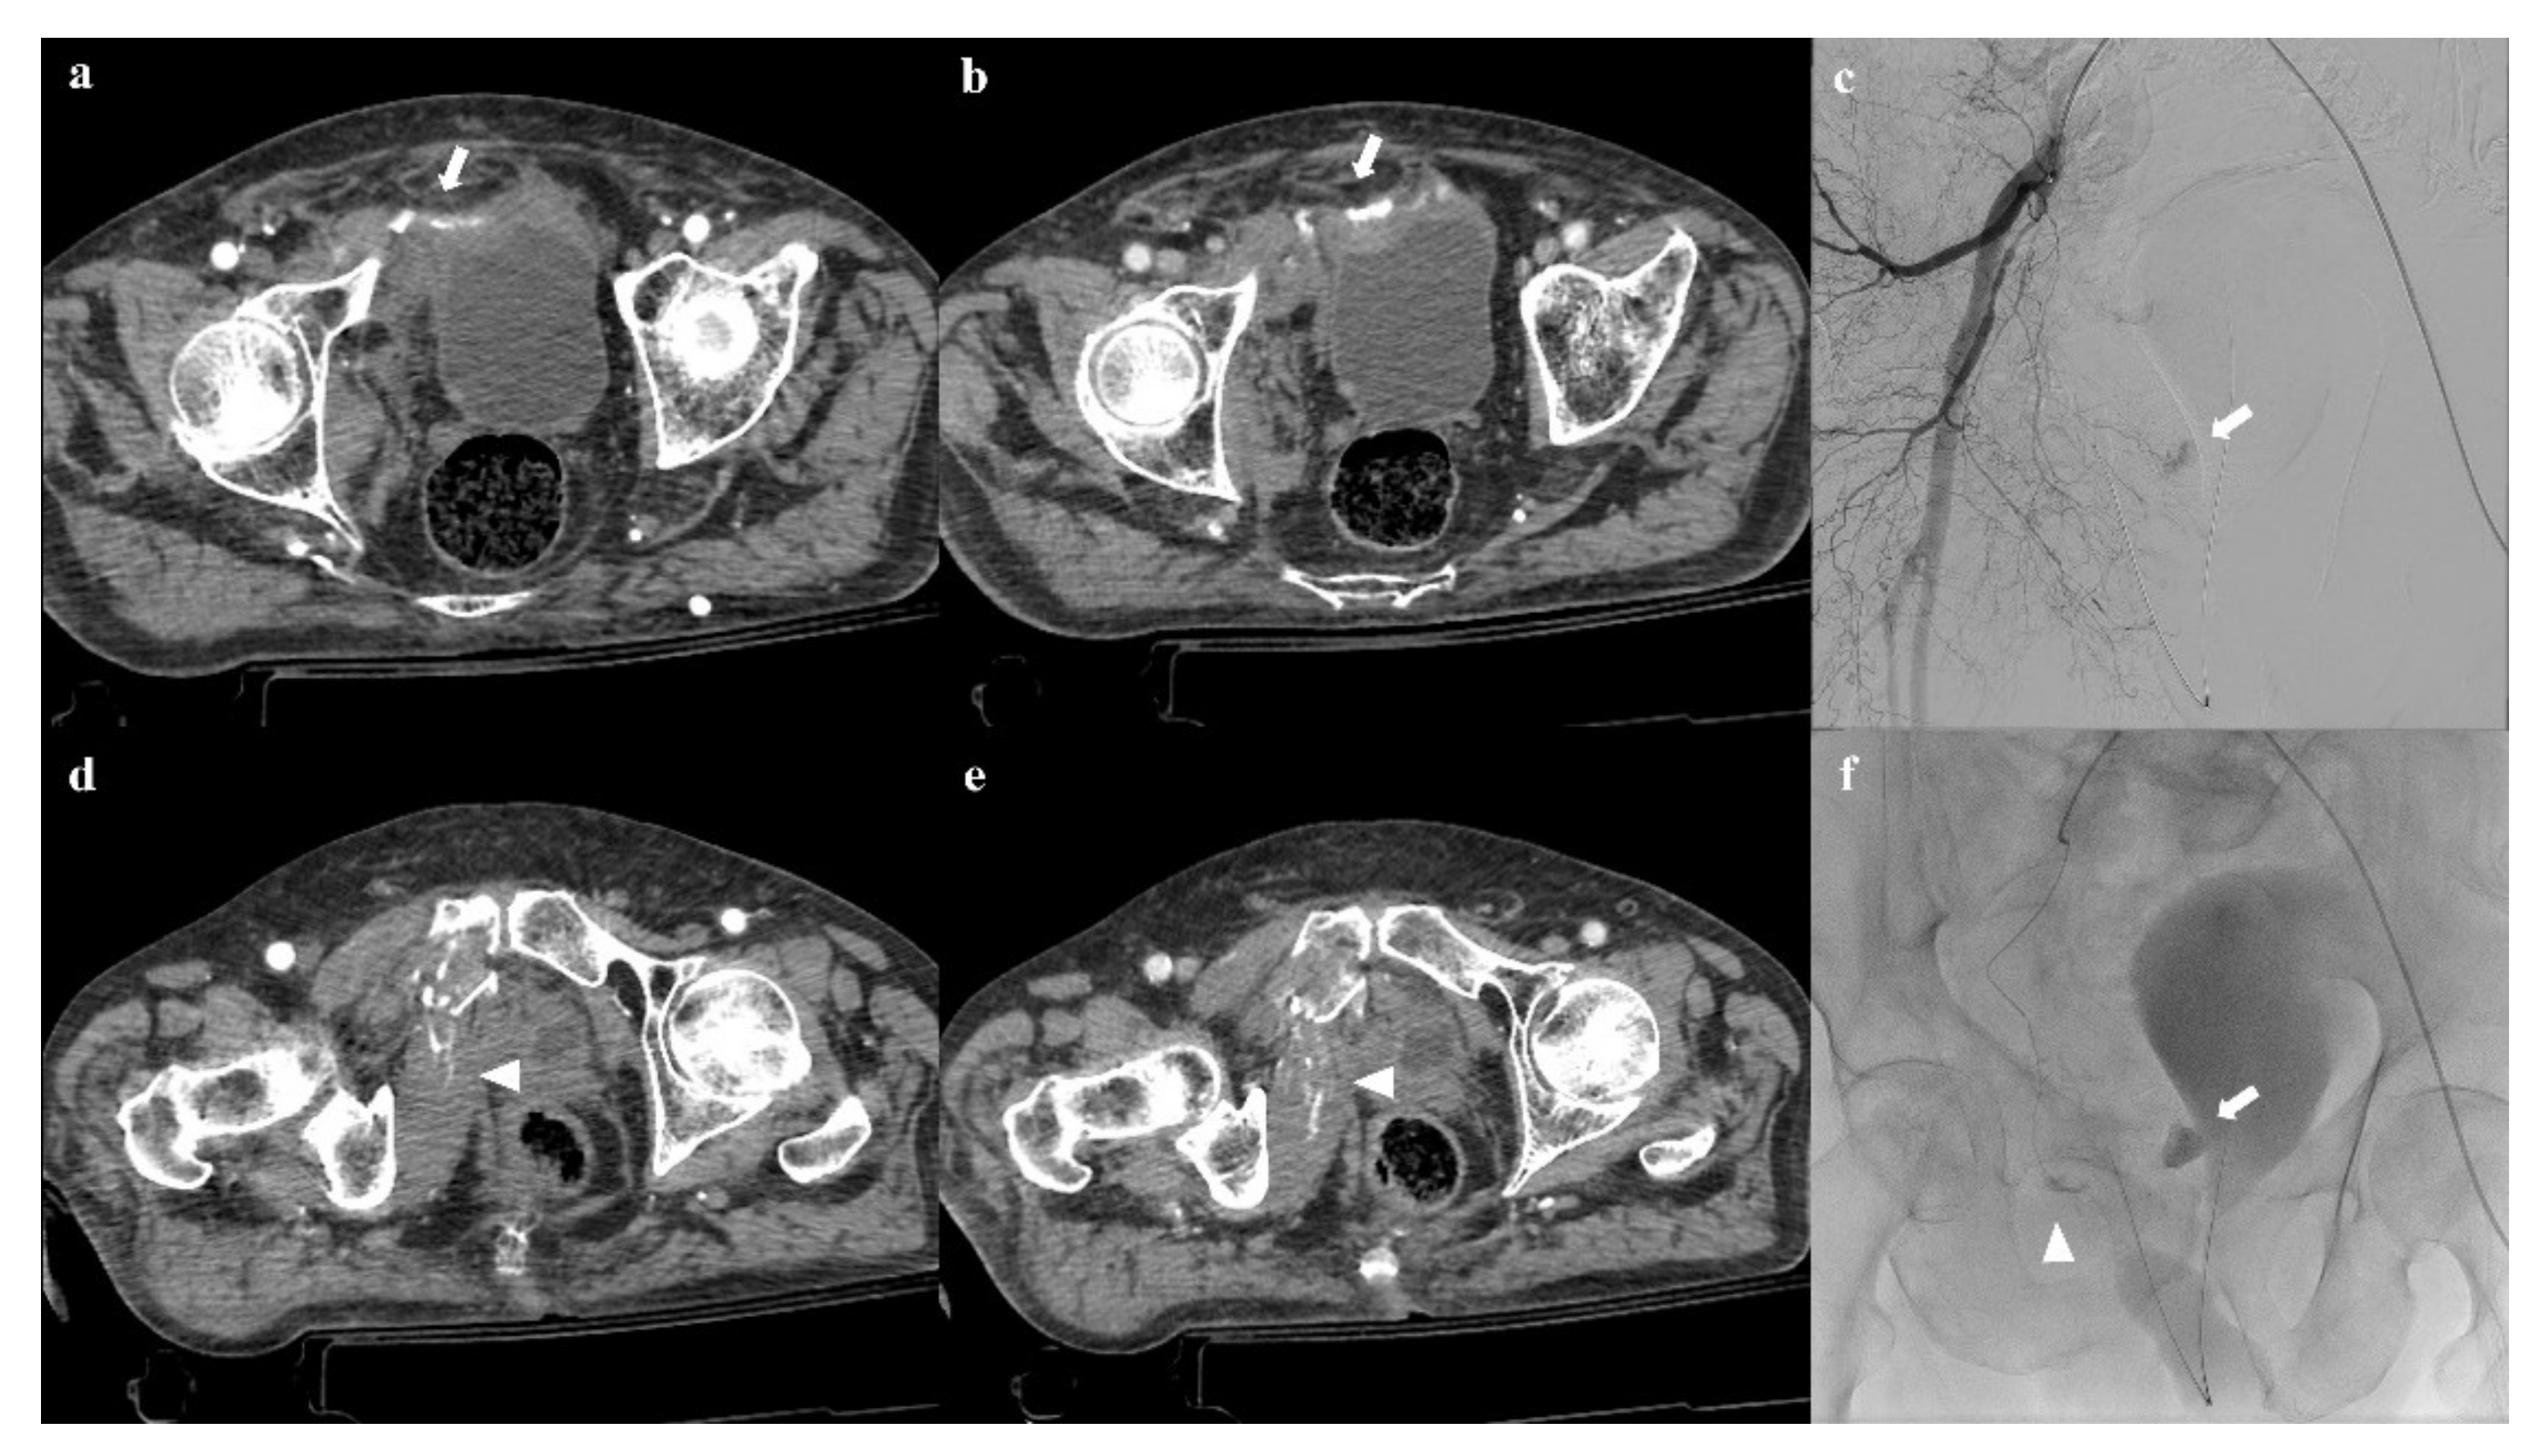

6.1. Vascular Complications

- Raniga, S.B.; Mittal, A.K.; Bernstein, M.; Skalski, M.R.; Al-Hadidi, A.M. Multidetector CT in vascular injuries resulting from pelvic fractures: A primer for diagnostic radiologists. Radiographics 2019, 39, 2111–2129. [Google Scholar] [CrossRef]

- Yoon, W.; Kim, J.K.; Jeong, Y.Y.; Seo, J.J.; Park, J.G.; Kang, H.K. Pelvic arterial hemorrhage in patients with pelvic fractures: Detection with contrast-enhanced CT. Radiographics 2004, 24, 1591–1605. [Google Scholar] [CrossRef] [PubMed]

- Baghdanian, A.H.; Armetta, A.S.; Baghdanian, A.; LeBedis, C.A.; Anderson, S.W.; Soto, J.A. CT of major vascular injury in blunt abdominopelvic trauma. Radiographics 2016, 36, 872–890. [Google Scholar] [CrossRef]

- Iacobellis, F.; Ierardi, A.M.; Mazzei, M.A.; Magenta Biasina, A.; Carrafiello, G.; Nicola, R.; Scaglione, M. Dual-phase CT for the assessment of acute vascular injuries in high-energy blunt trauma: The imaging findings and management implications. Br. J. Radiol. 2016, 89, 20150952. [Google Scholar] [CrossRef] [PubMed] [Green Version]